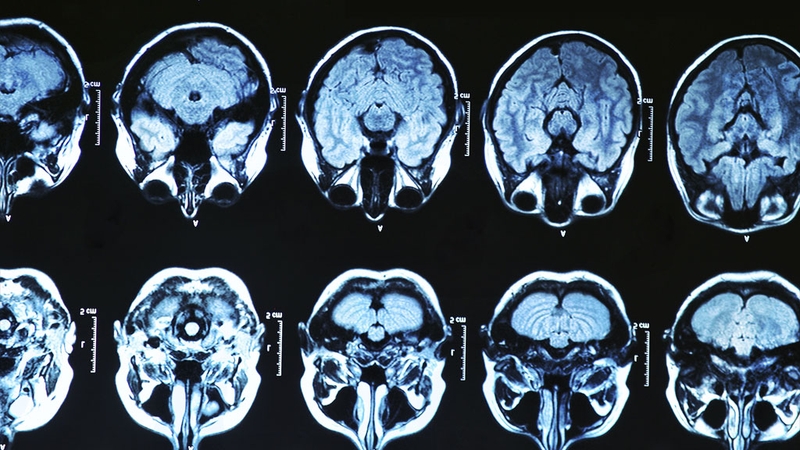

During adolescence, the brain undergoes widespread re-wiring that involves "synaptic pruning".

The new study, based on a genetic analysis of nearly 65,000 people from around the world, pinpointed a defective gene that appears to trigger excessive pruning.

Scientists believe it is this that underlies the symptoms of schizophrenia, a severe psychotic condition marked by a loosening grip on reality, delusions, paranoia and hallucinations.

Brains of people with the disease also tend to have a thinner cerebral cortex, the outer layer of neural tissue that processes sensory information and plays a key role in thinking and consciousness, with fewer synapses, or connections.